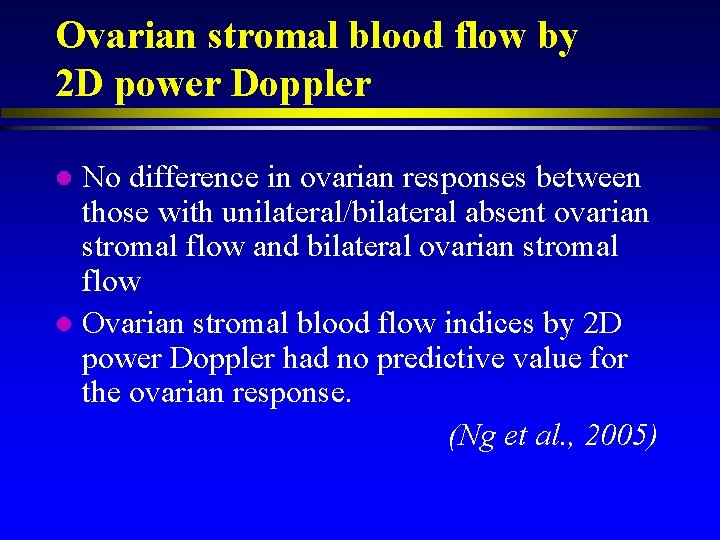

Ovarian stromal blood flow by 2 D power Doppler No difference in ovarian responses between those with unilateral/bilateral absent ovarian stromal flow and bilateral ovarian stromal flow l Ovarian stromal blood flow indices by 2 D power Doppler had no predictive value for the ovarian response. (Ng et al. , 2005) l